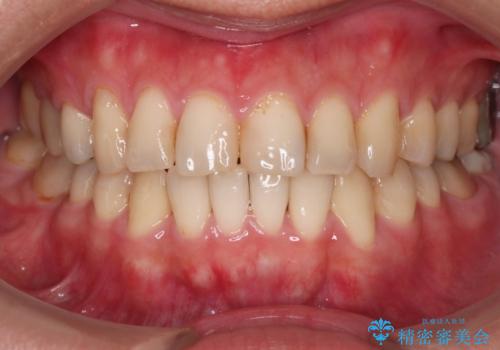

[マウスピース矯正] がたがたの歯並びをきれいにしたい

![[マウスピース矯正] がたがたの歯並びをきれいにしたいの症例 治療前](https://seimitsushinbi.jp/wp/wp-content/uploads/2025/06/0d238550c8a0fddc4de7b2c337c6c786-500x350.jpg?v=1750323380)

![[マウスピース矯正] がたがたの歯並びをきれいにしたいの症例 治療後](https://seimitsushinbi.jp/wp/wp-content/uploads/2025/06/IMG_0002-2-500x350.jpg?v=1750323305)